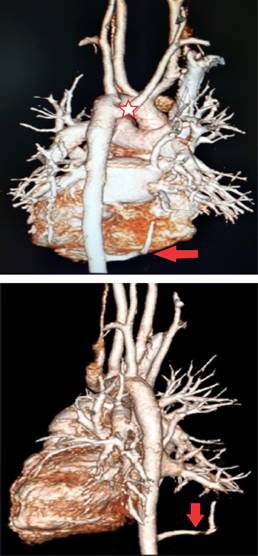

Estudios: difusión de monóxido de carbono (DLCO) 7.5 mL/min/mmHg (valor predicho 10.2), espirometría posbroncodilatador con una respuesta en volumen espiratorio forzado en el primer segundo (FEV1) del 16% y de más de 200 mL. La radiografía de tórax muestra un patrón atelectásico (Figura 1). Serie esofagogastroduodenal (SEGD) con presencia de reflujo grado III; en la angiotomografía de tórax (angio-TC) se observa una subclavia derecha aberrante (Figura 2), lo mismo que en la aorta descendente, también un vaso aberrante (Figuras 3 y 4).

Figura 2: Angiotomografía computarizada de tórax fase arterial: se observa la presencia de subclavia derecha aberrante (flecha) que discurre desde la cara posterior de porción proximal de aorta descendente hacia la derecha del paciente por detrás del esófago (E) y que reduce el calibre del mismo en forma considerable.

Figura 3: Angiotomografía computarizada de tórax en la cual se observa la presencia de hipervascularidad pulmonar que genera una lesión sólida muy pequeña (flecha) y vaso nutricio (V) que nace de la aorta torácica descendente (A) y se localiza cerca del diafragma, de 4 mm de diámetro que se dirige a la región basal del pulmón derecho.